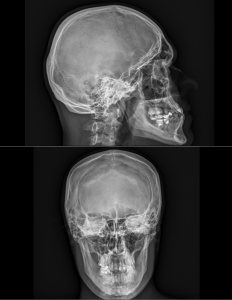

Princip vyšetření je založen na schopnosti rentgenového záření pronikat hmotou a dle vlastností jednotlivých tkání se specificky zeslabovat. Výsledkem je obraz zachycený na citlivý materiál – rentgenový film či detekční systém přístroje. Rentgenové vyšetření se hodí zejména k posouzení kostí a plic. Dále je možné např. z obsahu plynu ve střevech posoudit průchodnost střeva. Na snímcích lze hledat cizí kovová tělesa v těle.

Provádíme kompletní spektrum základních i speciálních skiagrafických vyšetření skeletu i měkkých částí lidského těla.

Ukázky RTG snímků